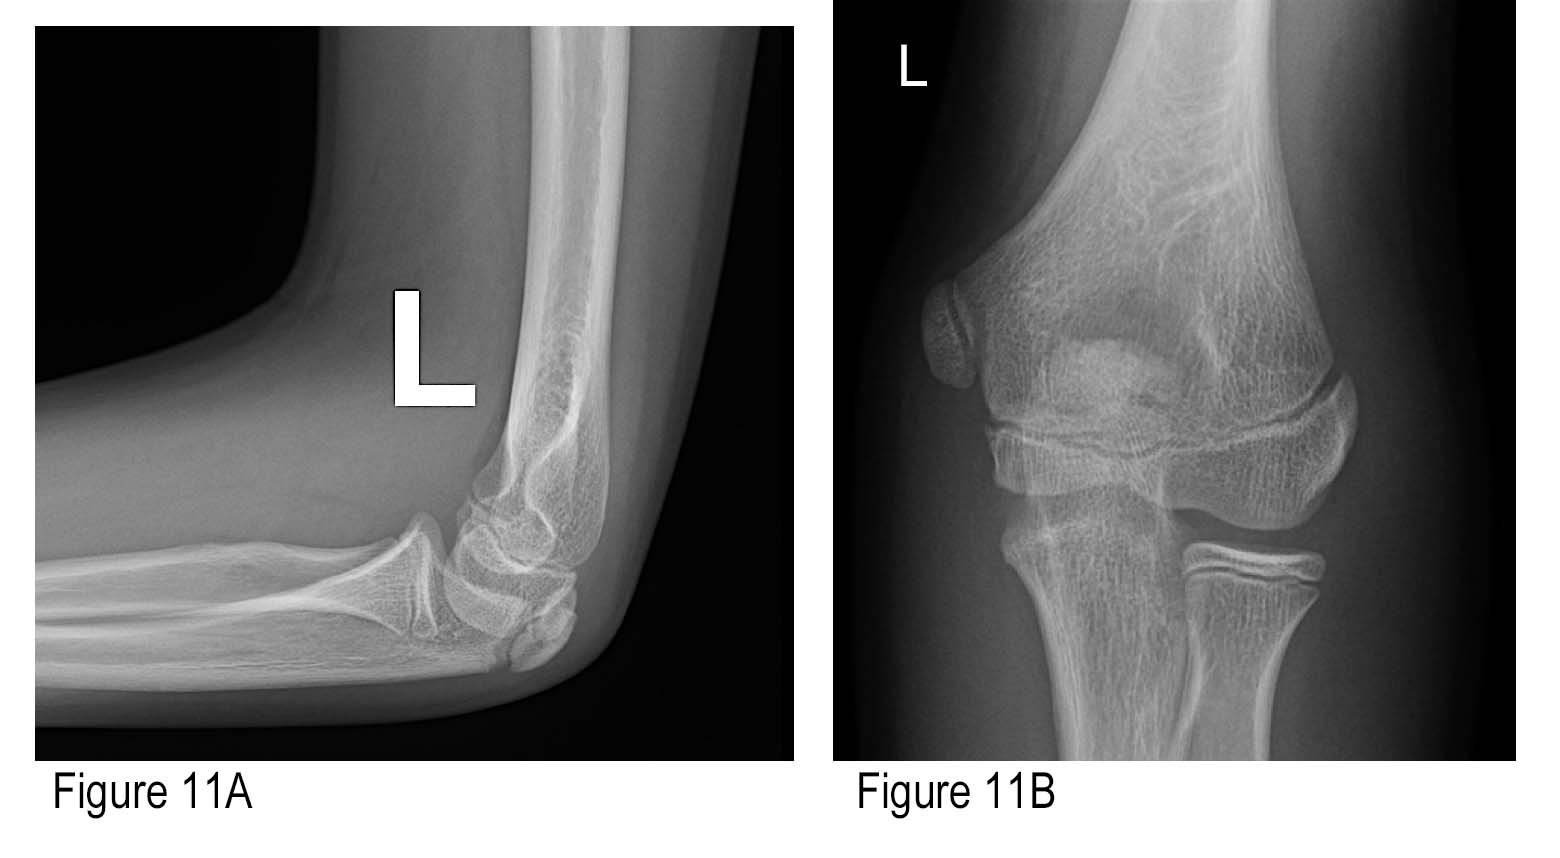

Left Elbow X Ray

File:X-ray of normal elbow by lateral projection.jpg - Wikipedia Elbow series | Radiology Reference Article | Radiopaedia.org X-ray Left Elbow Joint AP & Lateral View | Test Price in Delhi | Ganesh Diagnostic 12,736 Elbow X Ray Images, Stock Photos & Vectors | Shutterstock | Left Elbow X Ray